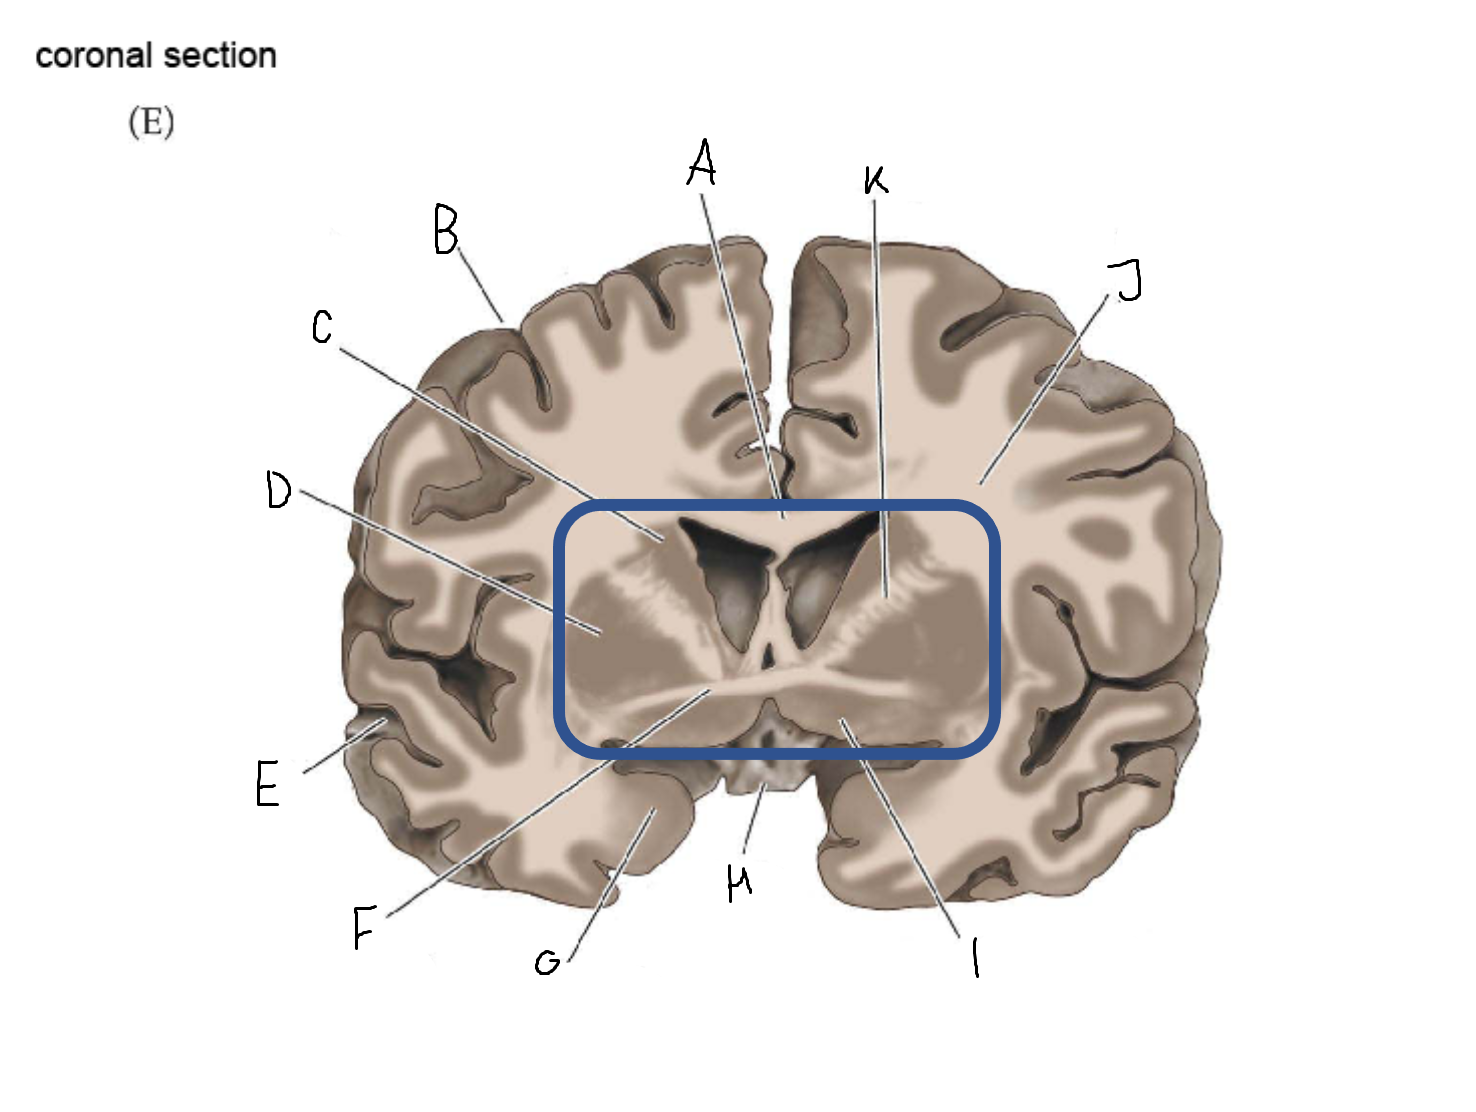

B

anterior horn of lateral ventricle

C

head of caudate nucleus

D

internal capsule (anterior limb)

E

putamen

F

globus pallidus

G

Thalamus

H

External capsule

I

internal capsule (posterior limb)

J

tail of caudate nucleus